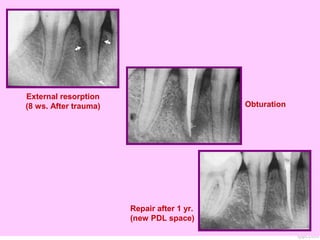

External resorption

(8 ws. After trauma) Obturation

Repair after 1 yr.

(new PDL space)

FunctionFunction of cementum:ofcementum: Repair any damaged area of the root resulted from resorption.

External resorption (8 ws.After trauma) Obturation Repair after 1 yr. (new PDL space)